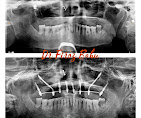

• Dental Implants & Full Mouth Implants: Permanent solutions for missing teeth, including advanced Zygomatic Implants for patients with bone loss.